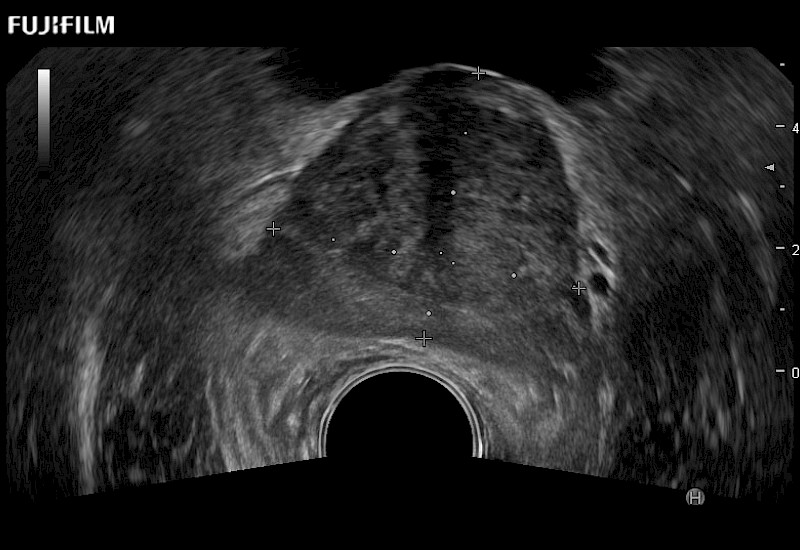

Exclusive 200° FOV end-fire prostate biopsy transducer.

Main Specifications:

Provides real-time imaging of both the sagittal and transverse planes